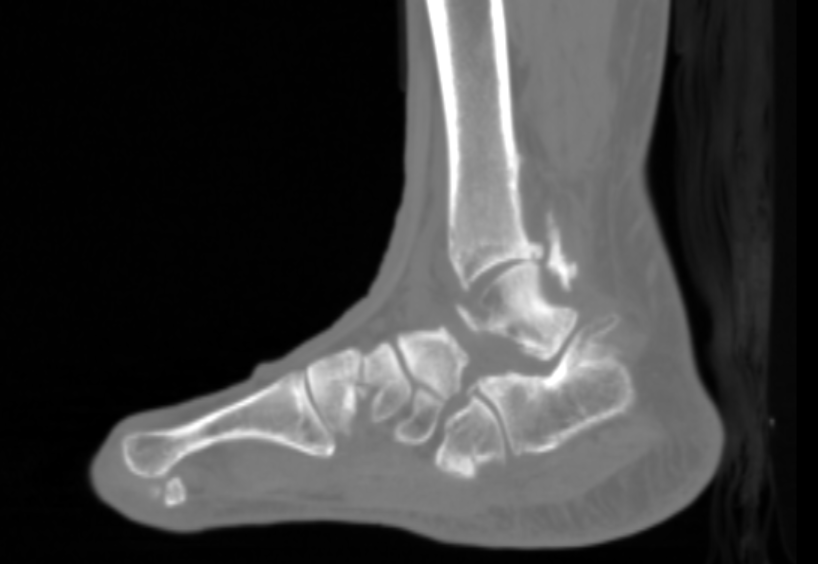

Neovision a développé un algorithme de landmarking, à savoir, l’identification de points anatomiques stratégiques pour chaque os (dôme tibial, dôme talaire dans le cadre de la cheville par exemple). Pour cela, nous nous sommes basés sur les connaissances des chirurgiens orthopédiques pour créer une base de données de points anatomiques nécessaires au bon déroulement de la chirurgie.